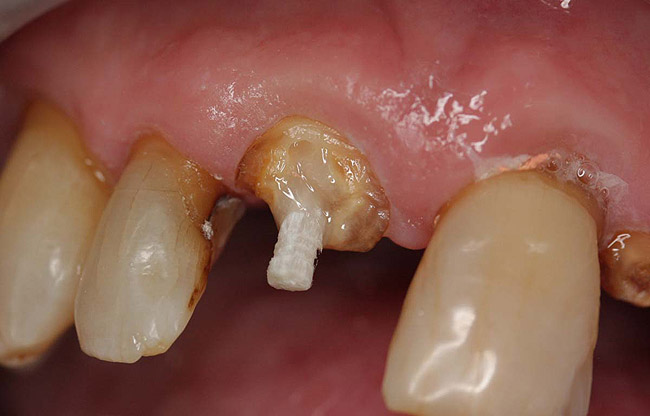

Case 1

A Class IN maxillary bicuspid was previously restored with a fiber post and an all-porcelain crown (Figure 1). The forces of the oral environment resulted in fracture of the fiber post and crown failure. The remaining fiber post in the root was removed, and anti-rotational areas were prepared for a cast post (Figure 2). A gold cast post was constructed at a dental laboratory, using an indirect technique (Figure 3). A porcelain-fused-to-metal (PFM) crown was constructed with a bevel finish to provide a ferrule and reduce forces on the post (Figure 4 and Figure 5).

Figure 2  Same second bicuspid as Figure 1 after removal of the fractured fiber post.

Figure 2

Figure 3  Cast post to restore the second bicuspid.

Figure 3

Figure 4  The cast post was cemented.

Figure 4

Figure 5  The final crown.

Figure 5